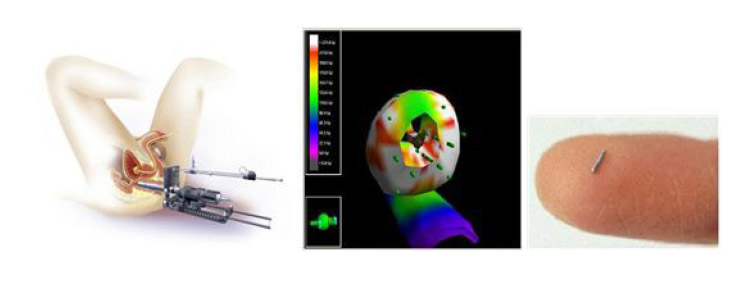

前⽴腺癌密封⼩線源永久挿⼊治療装置

VariSeed Ver.8.0 (ユーロメディック社)

早期前⽴腺癌に対し⼩さなヨウ素(I-125)の棒状線源を会陰部から埋め込むことによって、低侵襲で障害の少ない根治治療が可能となりました。経直腸超⾳波誘導下に前⽴腺内に放射線ヨウ素の⼊ったチタンカプセルを60-100個埋め込みます。カプセルから⾮常に弱いエネルギーの放射線が前⽴腺近傍のみにゆっくりと放出され、癌を治療します。周囲への被爆もなく、通常3泊4⽇⼊院での治療となります。